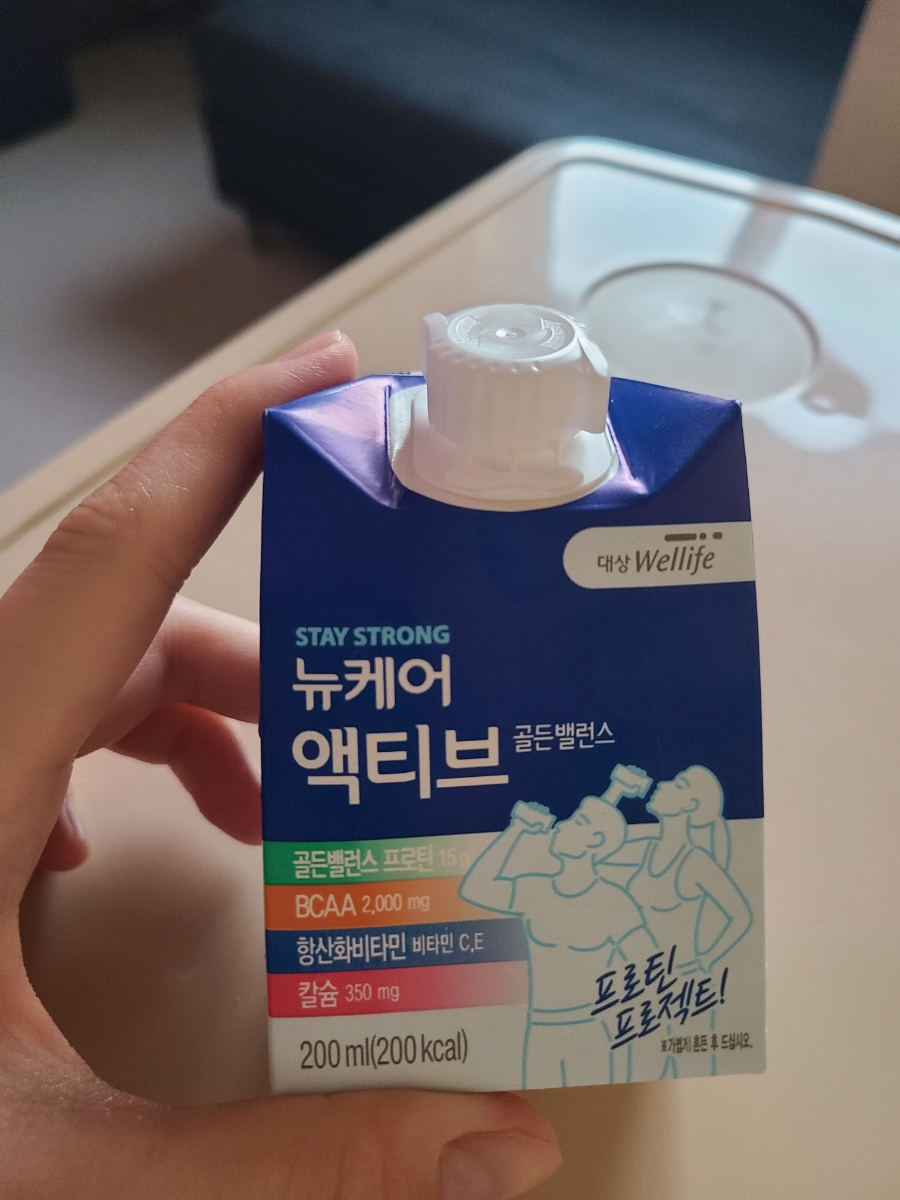

흰죽으로는 영양이 안 되니까 천천히 먹어 보자. 걸쭉한 미숫가루 맛이 나는 그림처럼 뒤집어 먹으면 목에 무리가 갈 것 같다.